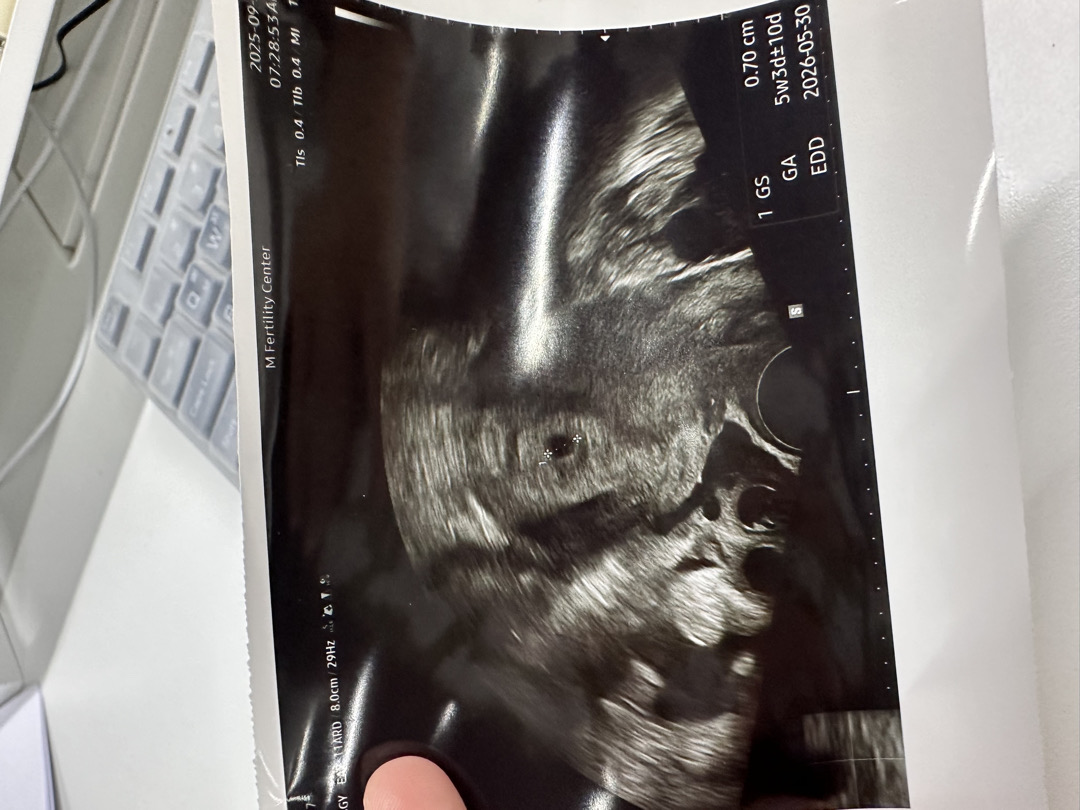

5주 3일차 아기집!

5주 3일차 0.7cm 아기집만보고왔어요... 다음 병원예약은 14일인데.... 쓰리라인임테기를 계속 하는게맞을까욤...